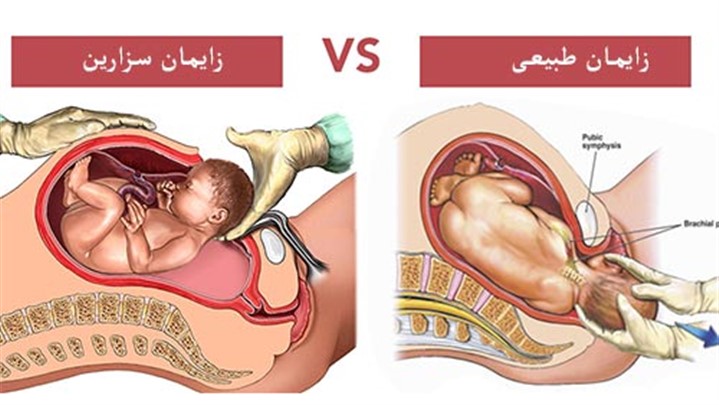

- عدم نیاز به داروی بیهوشی مانند سزارین